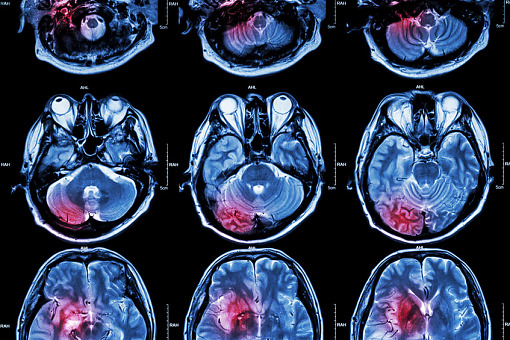

Australijscy badacze na łamach „The Lancet” wykazali, że objętość zmian niedokrwiennych oceniana w tomografii komputerowej była istotnie mniejsza w przypadku tenekteplazy niż alteplazy we wczesnym (do 4,5 godziny od początku objawów) leczeniu udaru niedokrwiennego mózgu; rezultaty kliniczne okazały się podobne. Wyższość badanego leku polega na prostocie i szybkości podawania (pojedynczy, 10-sekundowy bolus w łatwej do zapamiętania dawce 0,25 mg/kg masy ciała).

Przeprowadzone przez kanadyjskich naukowców badanie ACT objęło aż 1600 pacjentów z ostrym udarem niedokrwiennym kwalifikujących się do trombolizy; przydzielono ich losowo do otrzymywania alteplazy lub tenekteplazy. Wykazano, że obie interwencje są równoważne co do działania klinicznego. Po 90 dniach wynik w zmodyfikowanej skali Rankina (mRS) w zakresie 0–1 osiągnięto u 36,9 proc. pacjentów w grupie tenekteplazy i u 34,8 proc. w grupie alteplazy. Nie zaobserwowano różnicy między grupami w żadnym z drugorzędowych punktów końcowych. Pod względem bezpieczeństwa oba leki wyglądały podobnie: zgon wystąpił u 15,2 proc. w porównaniu z 15,6 proc., objawowy krwotok śródmózgowy u 3,4 proc. vs 3,1 proc., konieczność przetaczania krwi w 0,7 proc. vs 0,8 proc., a jakiekolwiek krwawienie widoczne w badaniach obrazowych w 19,4 proc. vs 20,2 proc. Autorzy podkreślają dodatkowo, że nie zaobserwowano żadnej heterogeniczności efektu oraz że nie znaleziono żadnej podgrupy, w której tenekteplaza okazała się mniej skuteczna.